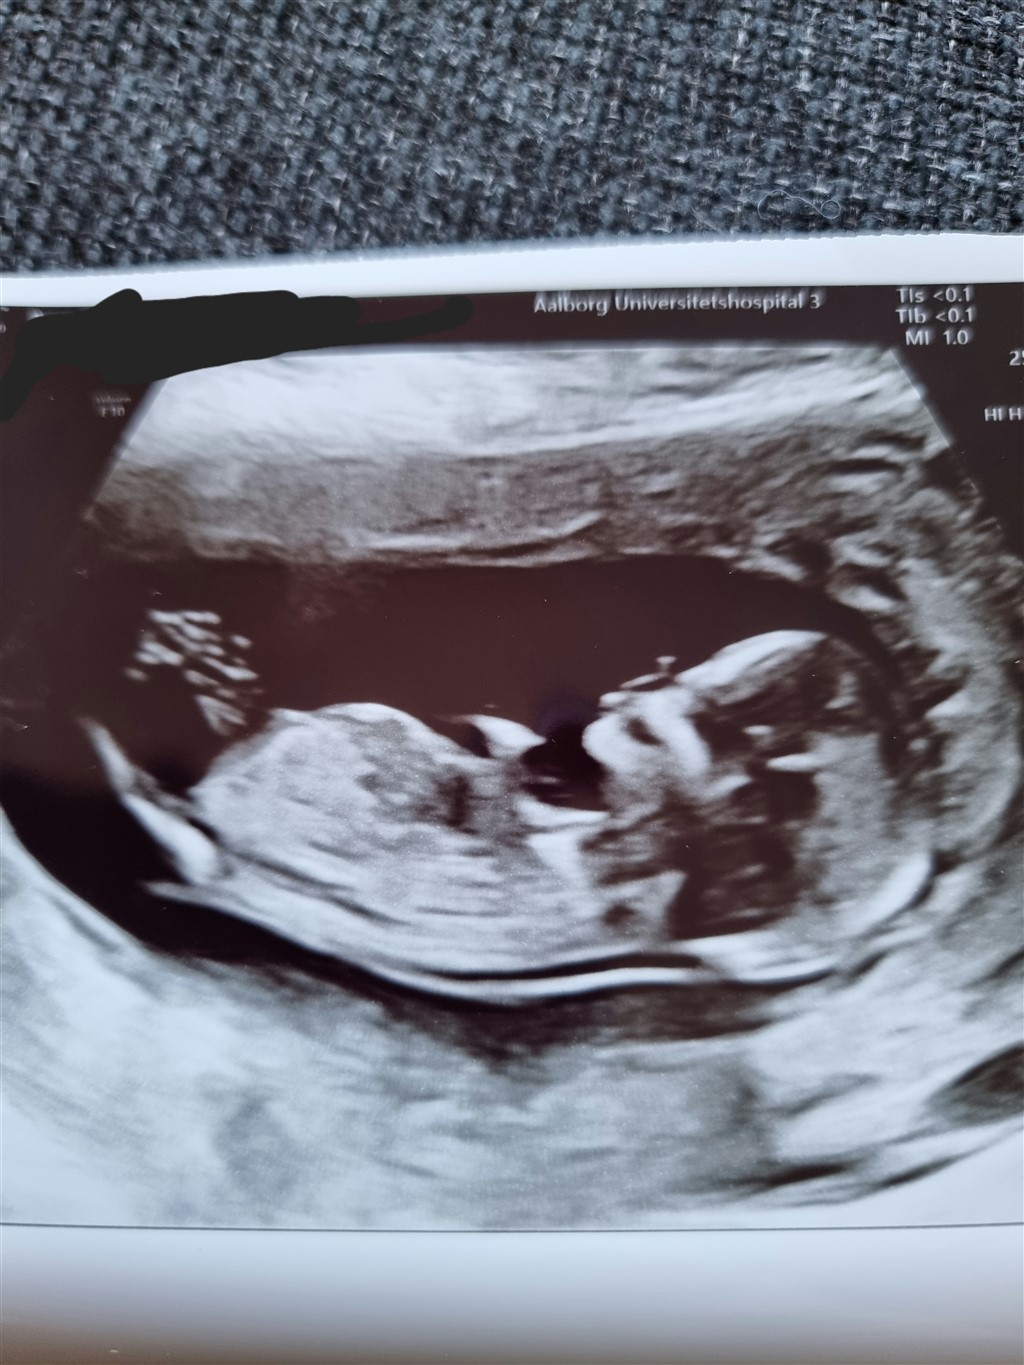

Kan nogen se om dette skulle være en dreng eller en pige? Er 13+6 på billederne.

Vedhæftede fotos (klik for at se i fuld størrelse)

Vil forsigtigt gætte pige

Jeg vil også sige pige ud fra skull theory, syne/ nub er svær at se.